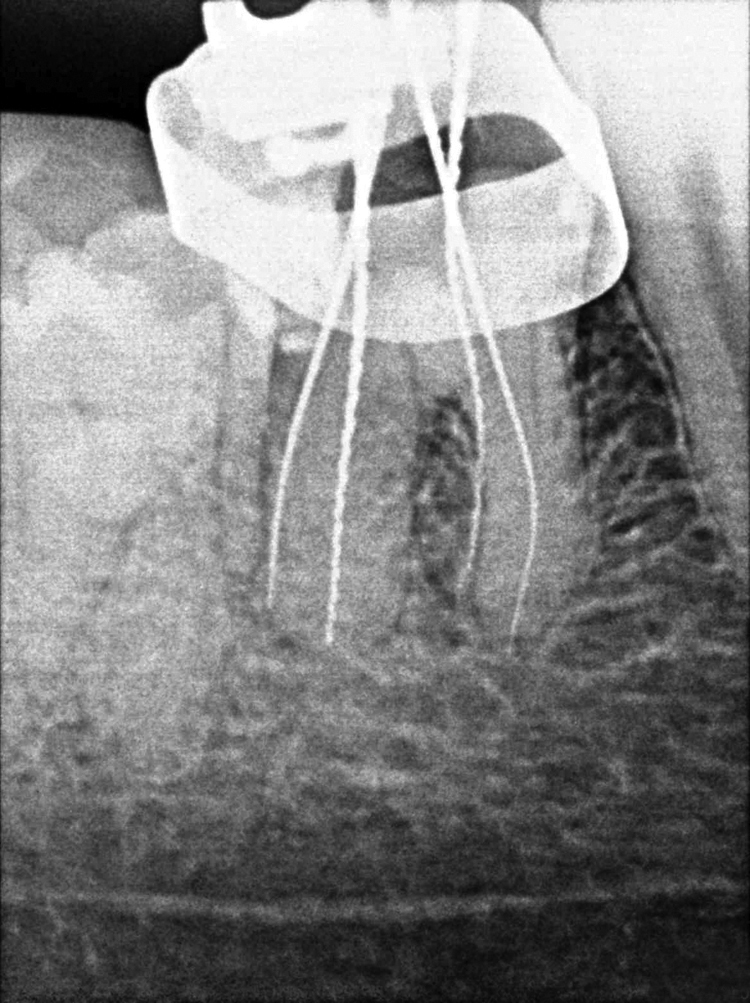

Prior to any further treatment, an orthodontic band was placed around 46 to stabilise the tooth and prevent further propogation of the fracture line [Table/Fig-2]. Then root canal therapy was resumed. Access opening was refined, and four canal orifices were located, two mesial and two distal. The working length was determined [Table/Fig-3] and the canals were cleaned and shaped using crown-down technique with hand ProtaperTM instruments to size F1. A mastercone radiograph was taken [Table/Fig-4] and the canals were obturated with lateral condensation technique at the next sitting [Table/Fig-5].

Working length estimation radiograph for 46.